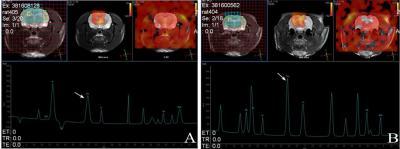

This is a proton magnetic resonance spectroscopy of the hippocampus and thalamus of early growth response protein 3 gene-transfected rats.Choline (Cho; arrow represents Cho peak) content was increased in the left hippocampus of schizophrenic rats (A) compared with bilateral hippocampi of control group (B).

(Photo Credit: Neural Regeneration Research)